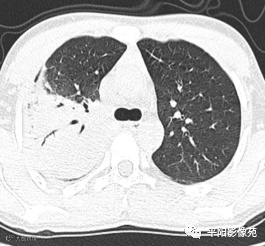

5天后复查X线片及CT:较前加重

影像特征:X线片右肺中上野片状高密度影,下缘以叶间裂为界,上缘及外侧缘模糊;CT位于右肺上叶后段,呈片状实变影,内见支气管影,边缘模糊。

影像诊断:右肺上叶大叶性肺炎。

①充血期:X线无阳性征象或仅表现为局限性肺纹理增粗;CT表现为边缘模糊的磨玻璃样阴影。②实变期:整个肺叶、大部分肺叶或肺段呈高密度阴影,阴影密度均匀,内可见支气管充气征,肺叶实变以叶间裂为界,边缘清楚。③消散期:大叶阴影密度减低,逐渐变为散在斑片状阴影,进而演变为索条状阴影,直至完全吸收。